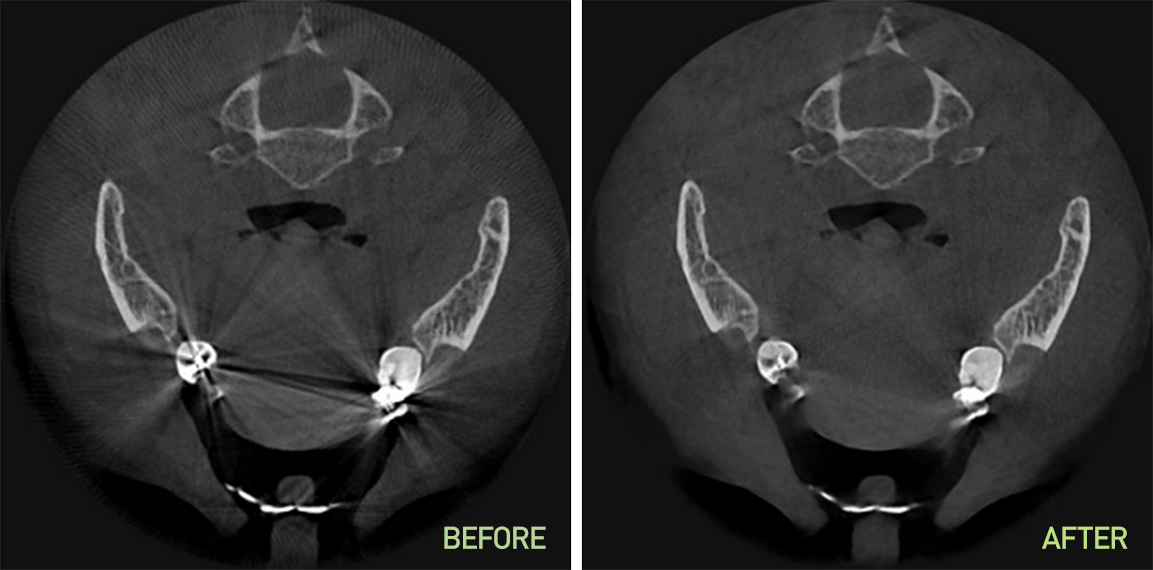

SMARF™

(Smart Metal Artifact Reduction Function)

Minimalizálja a fém okozta torzulásokat, így a protézisek sem rontják a képminőséget, és optimális felvételek készíthetők.